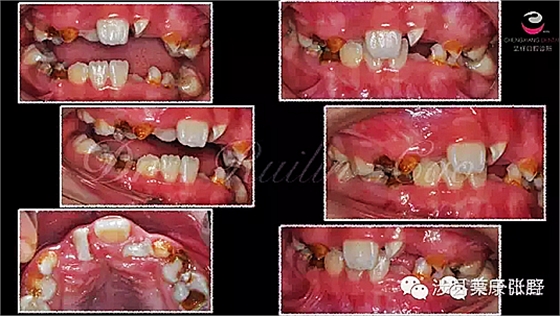

好多家長認(rèn)為乳牙反正要換,蛀牙不需要治療,等換牙就好了,真的是換牙就好了嘛?不治療會(huì)有什么危害呢?

讓我們來看一下吧

蛀牙會(huì)疼痛,非常痛。孩子可憐死了,影響吃飯。

![(VG08}R)0@])T5`)IIBPUD5.png (VG08}R)0@])T5`)IIBPUD5.png](/Mobile/UploadFiles/FCK/2017-04/6362664243054169673055611.png_280.jpg)

影響美觀,讓小朋友笑話。